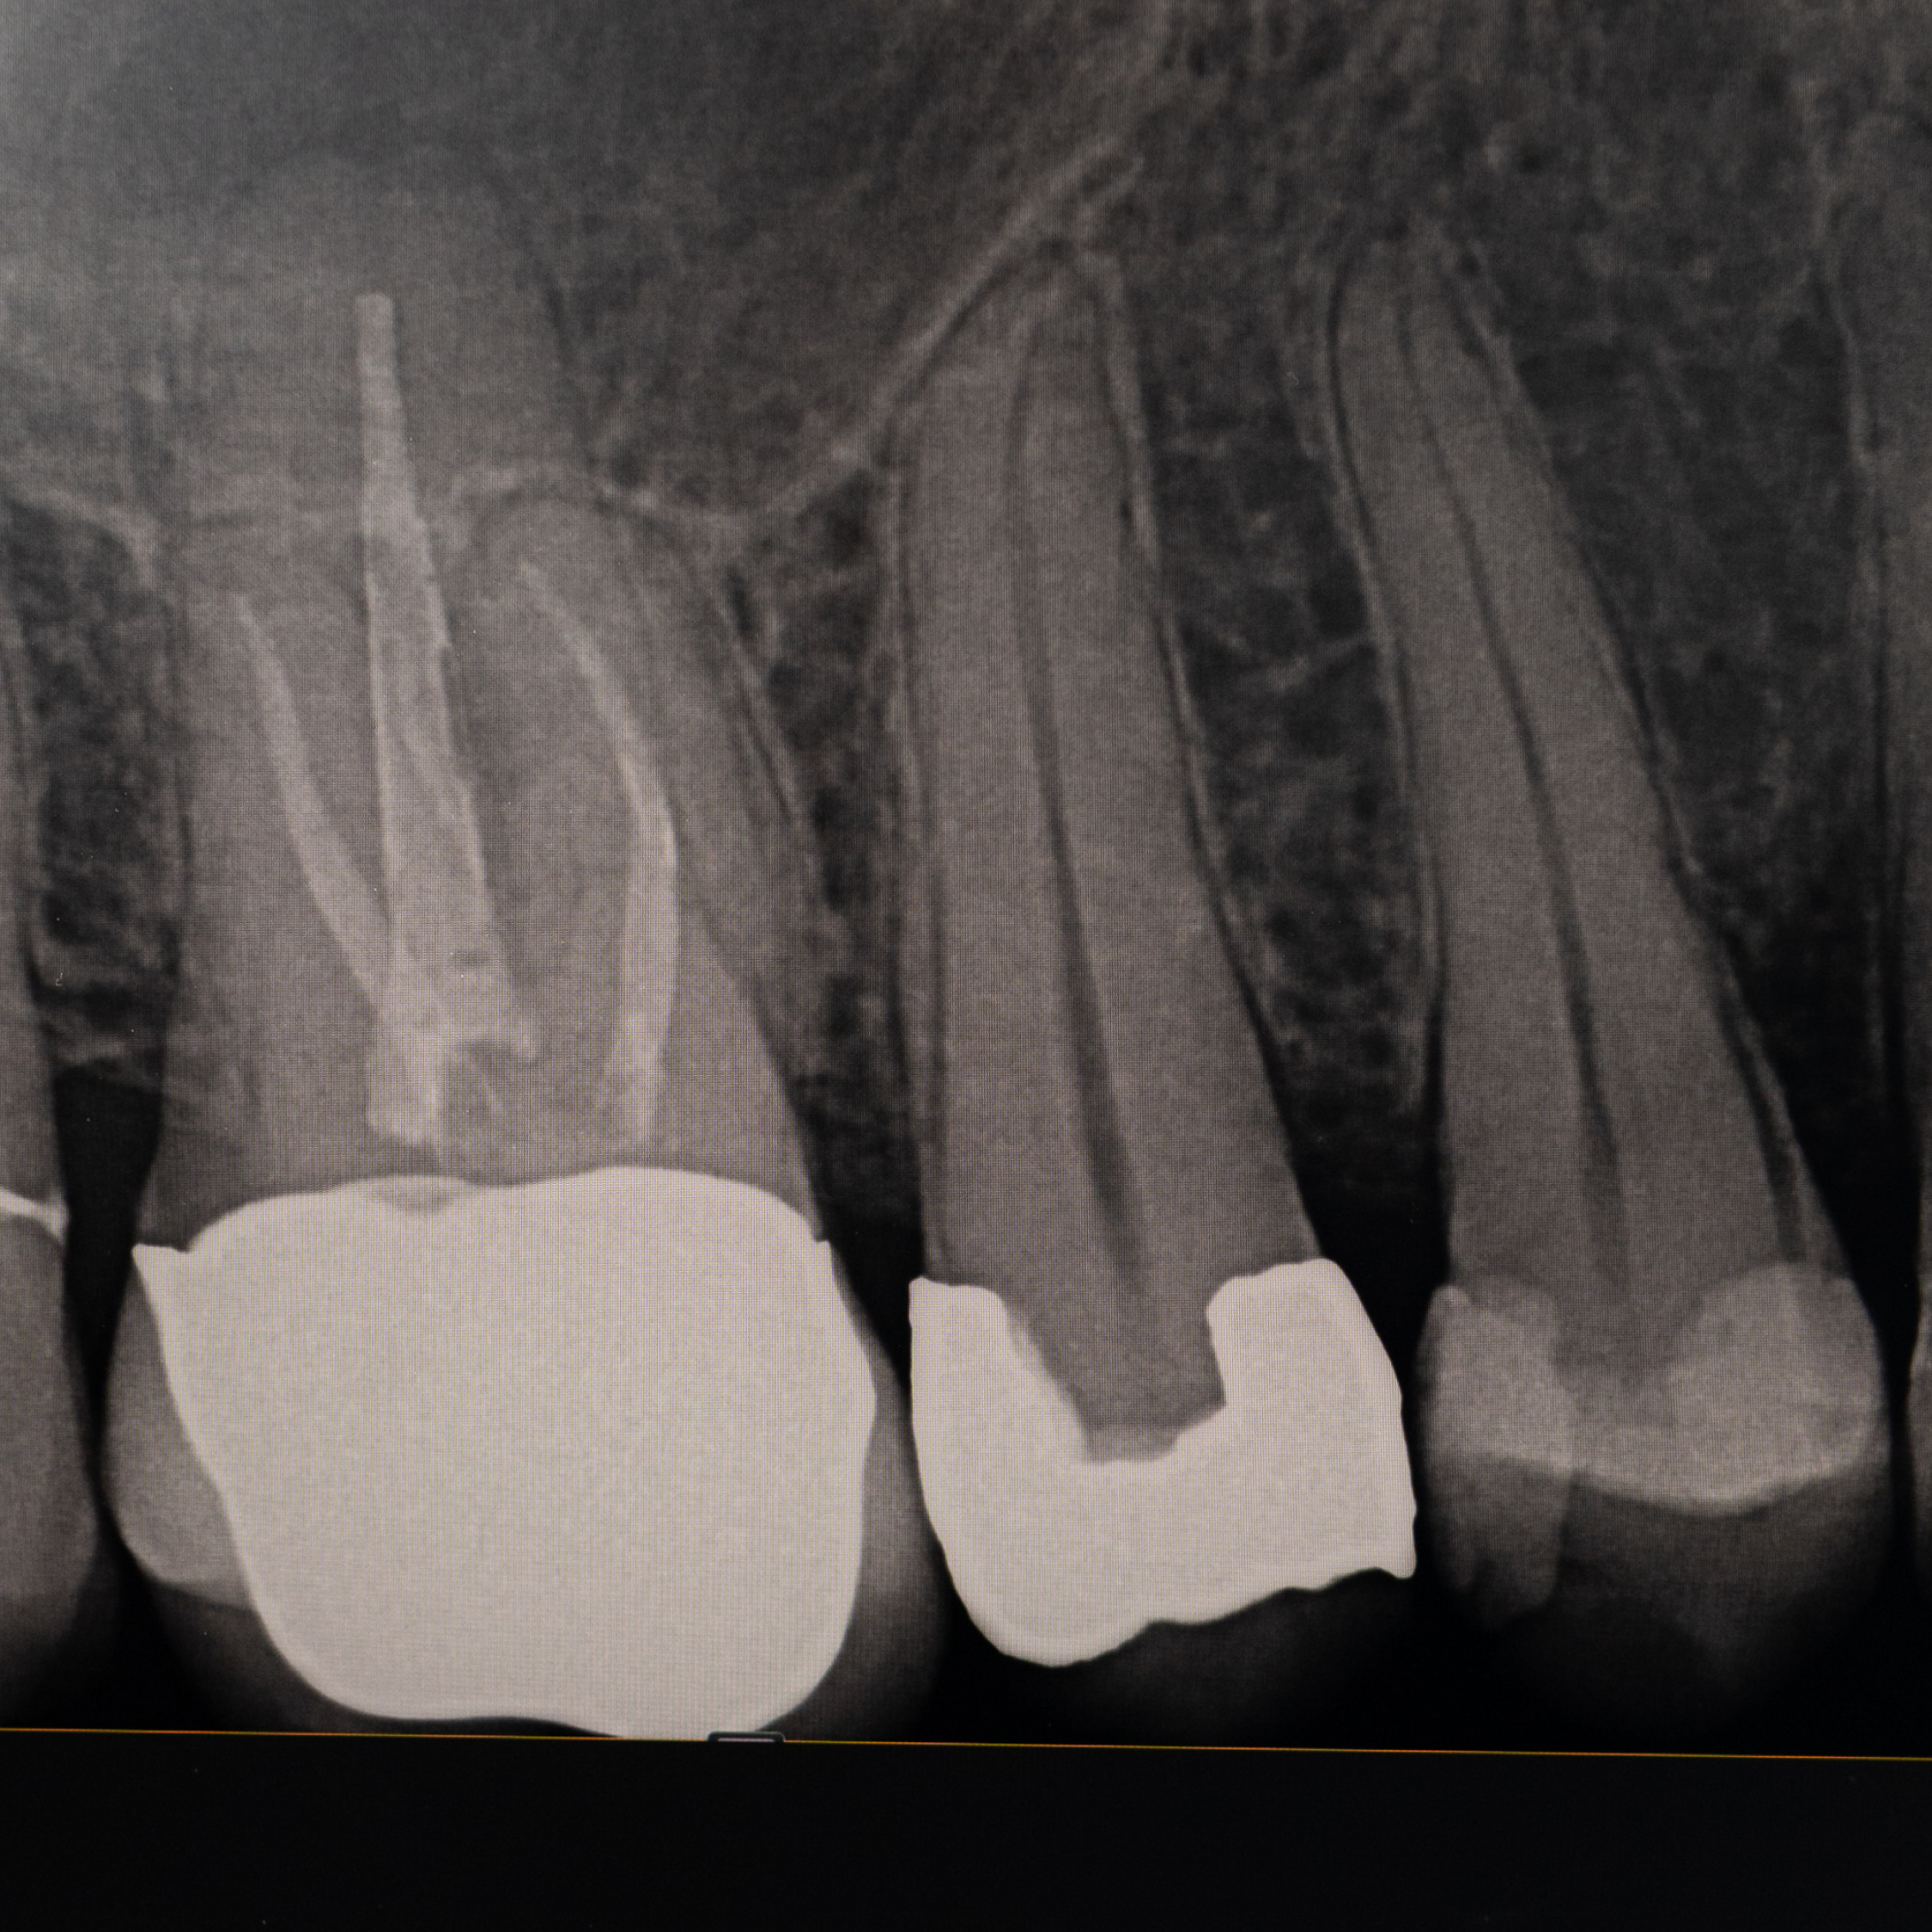

Root Canals: saving teeth, preserving smiles

Endodontic therapy, commonly known as root canals, is a vital procedure aimed at saving natural teeth that have become infected or severely damaged. Root canals maintain the integrity of your smile and overall oral health. By removing infected or damaged tissue, they provide relief from tooth pain and discomfort.

Treating infected teeth promptly helps prevent the spread of infection to surrounding teeth and tissues.

Our experienced dentists utilize advanced technology such as the Zeiss surgical and dental microscopes. These magnification tools enhance the precision and clarity of root canal procedures, ensuring minimal discomfort and optimal outcomes for you.